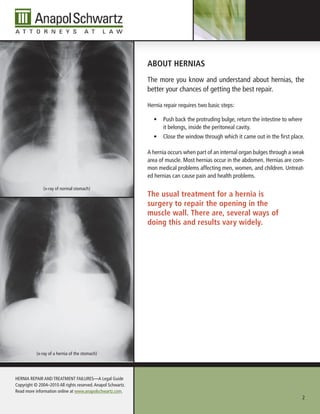

(x-ray of normal stomach)

the usual treatment for a hernia is

surgery to repair the opening in the

muscle wall. there are, several ways of

doing this and results vary widely.

(x-ray of a hernia of the stomach)